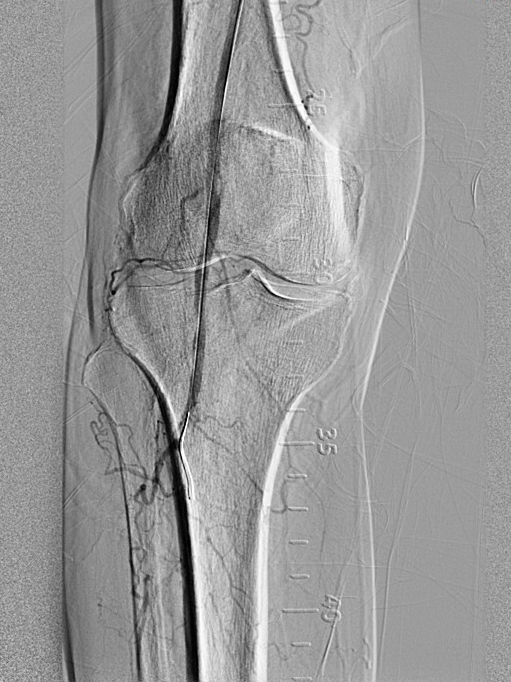

图2

股动脉下段闭塞,

图1为术前DSA,图2为术后DSA